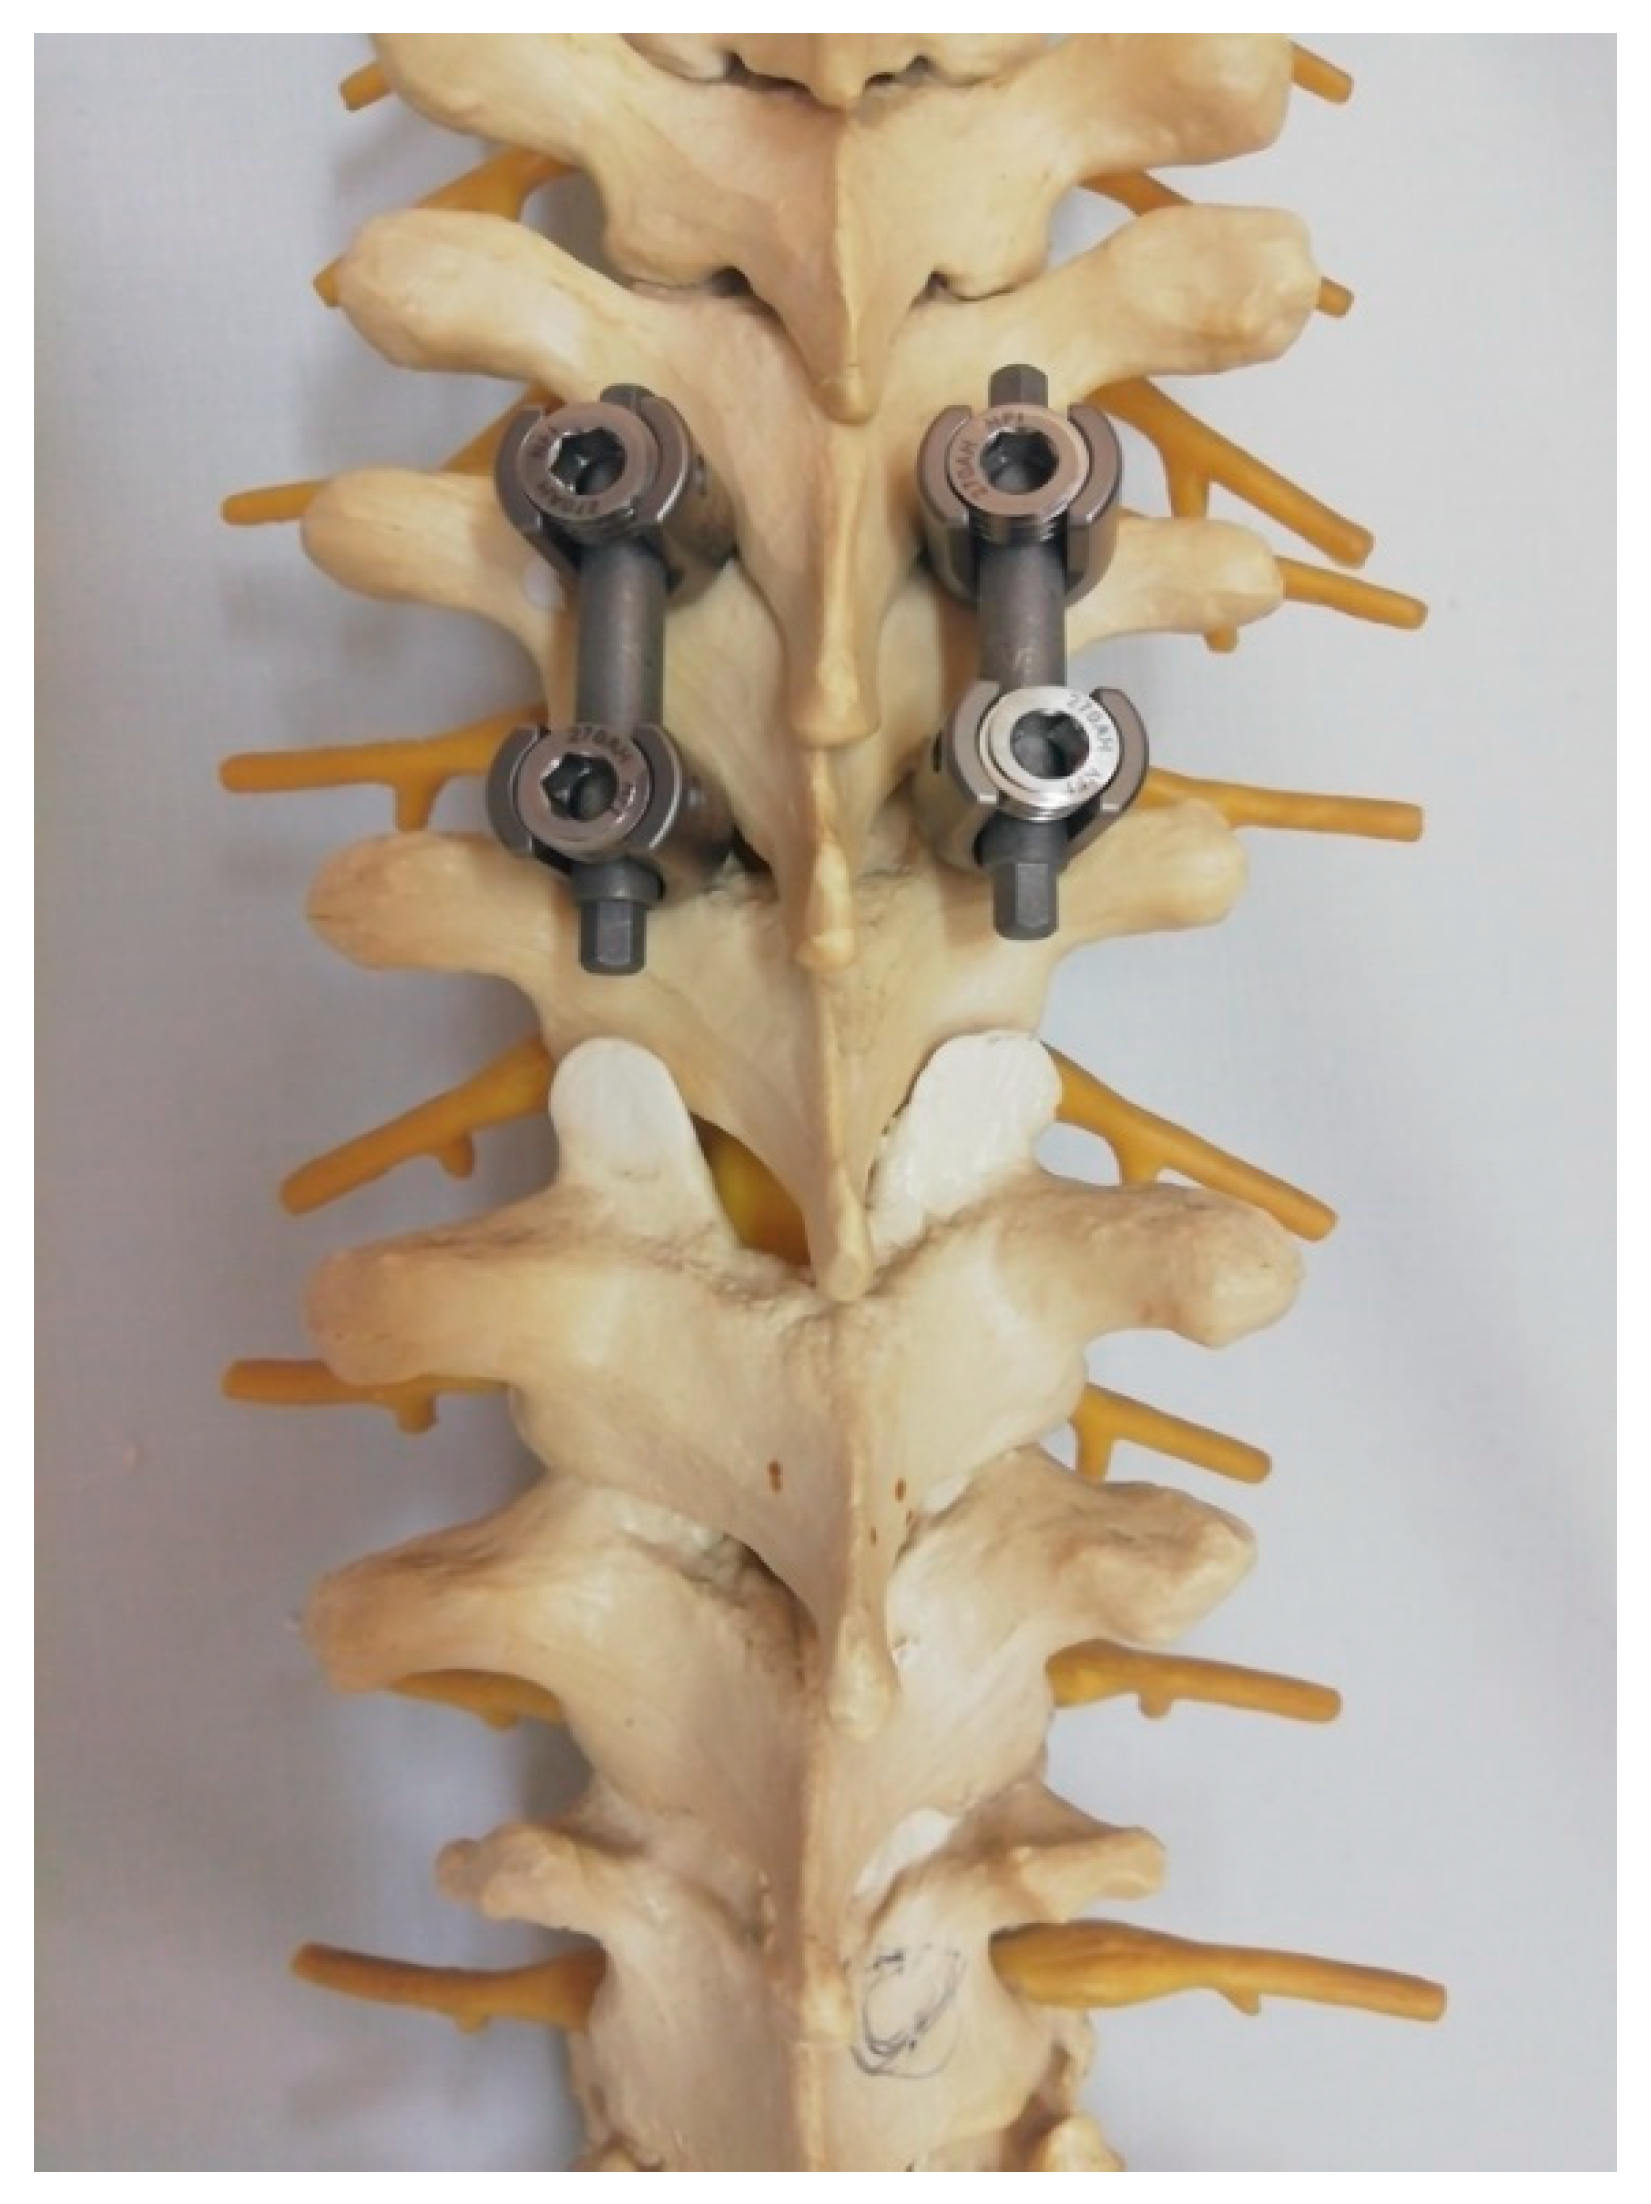

Figure 4.

Placement of proximal pedicle screws and fixation with two short temporary rods to facilitate grip during the reduction maneuver.